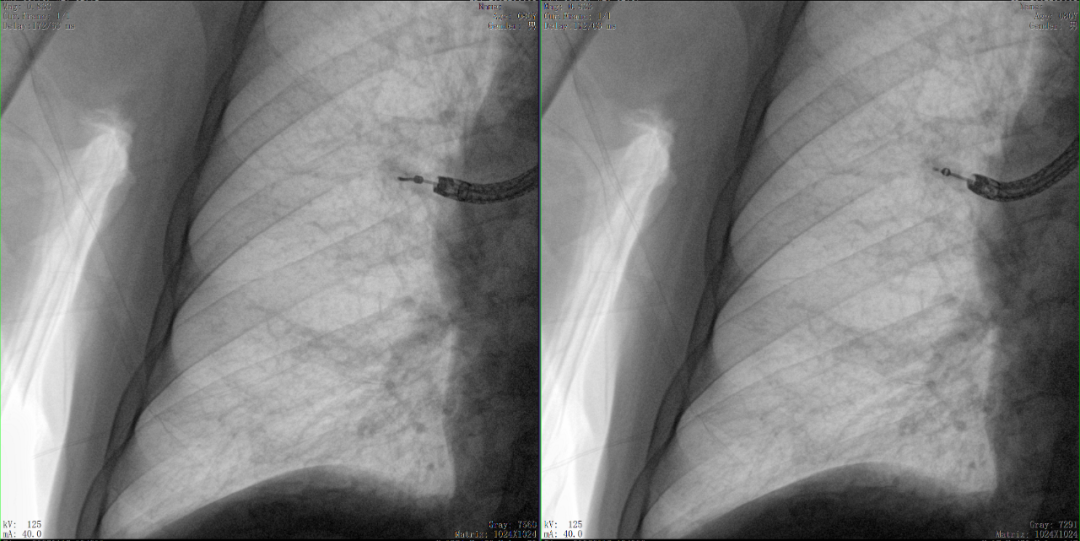

病例2 踝關(guān)節(jié)骨折復(fù)位(31歲)

在踝關(guān)節(jié)骨折復(fù)位手術(shù)中,用三維C可以更好地觀察骨折部位的復(fù)位情況:

正側(cè)位影像觀察脛腓聯(lián)合復(fù)位良好

從三維影像看,復(fù)位欠佳,貼合度不夠